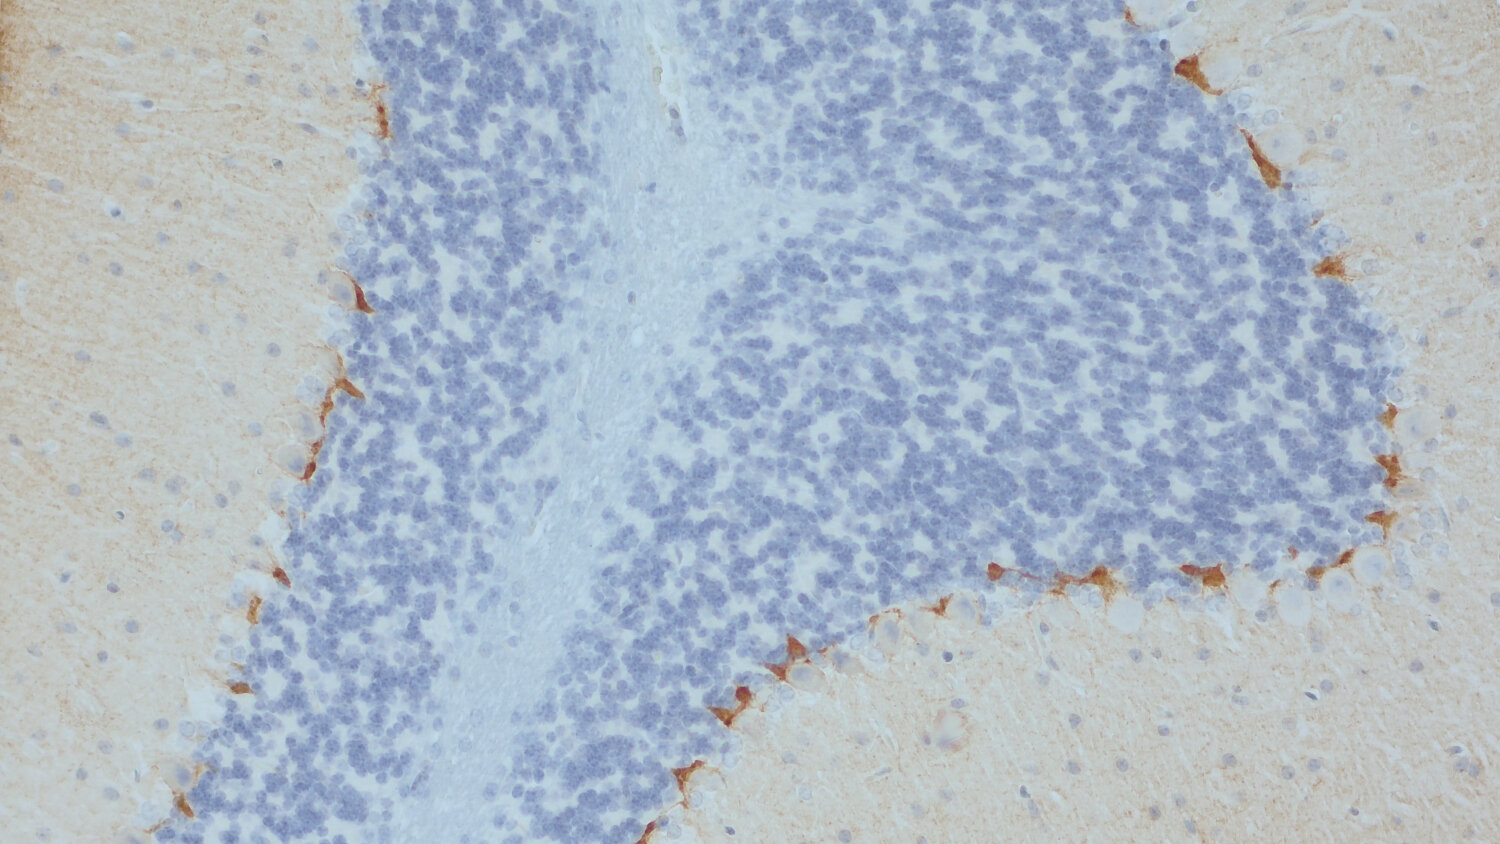

Specificity K.O. validated

IHC: 1 : 500 gallery

IHC-P: 1 : 500 gallery

Immunohistochemistry (IHC) on 4% PFA perfusion fixed tissue with 24h PFA post fixation. Immunoreactivity is usually revealed by fluorescence or a chromogenic substrate. Some antibodies require special fixation methods or antigen retrieval steps. For details, please refer to the ”Remarks” section.